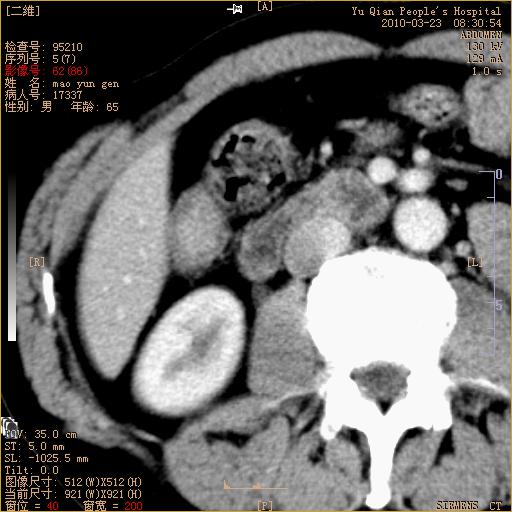

标题: CT25266:消瘦月余,前来肝部检查,请看看肠腔 [打印本页]

标题: CT25266:消瘦月余,前来肝部检查,请看看肠腔

肝区结肠占位,腺癌可考虑,建议肠镜活检。

升结肠肠壁增厚,不均强化,考虑升结肠腺癌可能性,建议肠镜检查。

1)考虑升结肠癌。2)右肾小囊肿。